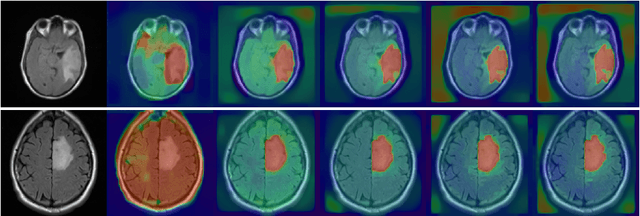

When studying the results of a segmentation algorithm using convolutional neural networks, one wonders about the reliability and consistency of the results. This leads to questioning the possibility of using such an algorithm in applications where there is little room for doubt. We propose in this paper a new attention gate based on the use of Chan-Vese energy minimization to control more precisely the segmentation masks given by a standard CNN architecture such as the U-Net model. This mechanism allows to obtain a constraint on the segmentation based on the resolution of a PDE. The study of the results allows us to observe the spatial information retained by the neural network on the region of interest and obtains competitive results on the binary segmentation. We illustrate the efficiency of this approach for medical image segmentation on a database of MRI brain images.